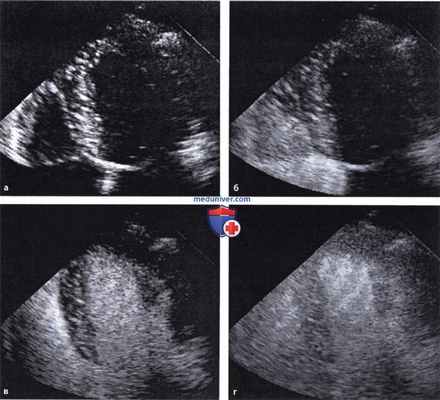

Выполнение контрастной ЭхоКГ:

а - Четырехкамерная позиция перед введением контрастного средства.

б - Контрастирование правых предсердия и желудочка после внутривенного введения контрастного средства.

в - Через 5-8 с (время транзита через легочный круг) происходит контрастирование также левого предсердия и левого желудочка.

г - Еще примерно через 3 с происходит проникновение микропузырьков в миокард и его контрастирование.